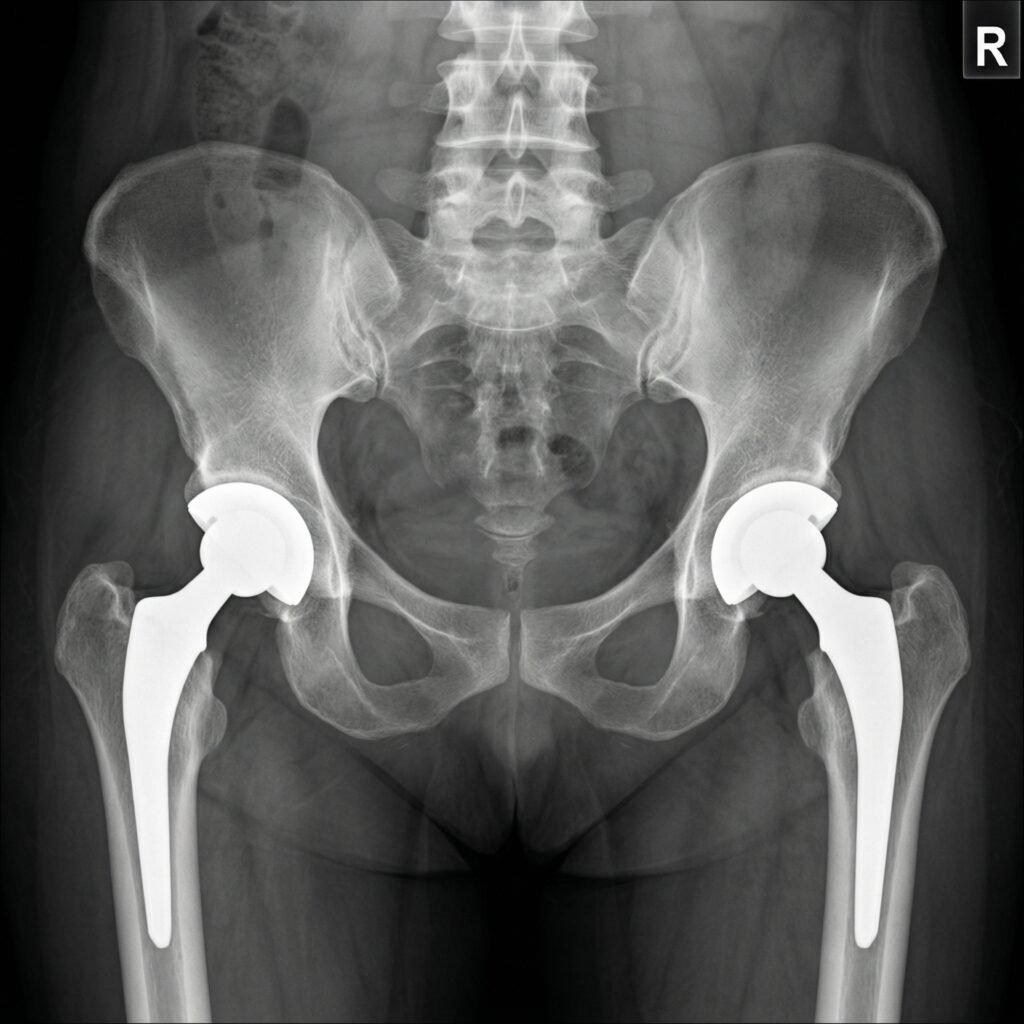

This advanced procedure involves removing the old implant and replacing it with a new, carefully selected prosthesis designed to restore joint function and stability. Due to its complexity, revision surgery requires precise planning, advanced surgical techniques, and expert care.

At Dr. Shreyansh Shukla’s clinic, detailed evaluation and imaging are used to assess the condition of the existing implant and surrounding bone. With a focus on accuracy, safety, and long-term outcomes, the procedure aims to relieve pain, improve mobility, and enhance overall quality of life.